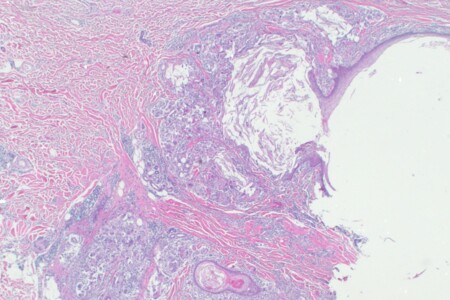

Cysty jsou dutiny vyplněné tekutinou nebo hutnou hmotou a mohou se tvořit kdekoliv v těle. Ve většině případů se tkáň začne cysticky měnit a vytvoří cystu bez jakékoliv zjevné příčiny. Platí to pro naprostou většinu cyst. Příznaky cysty závisejí na jejím umístění a typu. Pokud se cysta nachází pod kůží, většinou se projeví jako zduření nebo hrbol, u vaječníků může cysta vyvolat pocit napětí v břiše.

Cysta na vaječníku je označení pro jakoukoliv dutinku, která je vyplněna tekutinou a vyskytuje se v prostředí vaječníku. Většina cyst se vytváří běžně a za nějakou dobu sama zaniká. Některé cysty mohou však přetrvávat, být bolestivé a po jejich prasknutí způsobit krvácení. Proto by každá objevená cysta na vaječníku nebo častá bolest v podbřišku měly být pečlivě zkontrolovány lékařem a dále sledovány, popřípadě odoperovány.

Vaječníky jsou součástí pohlavního ústrojí ženy. Hlavní funkcí vaječníků je produkce pohlavních buněk, vajíček. Další funkcí vaječníků je produkce hormonů, které mají vliv na vznik sekundárních pohlavních znaků. Vaječníky jsou nezbytným orgánem pro tzv. ovariální cyklus, tedy pro rozmnožování. Bohužel i vaječníky mohou být postiženy různými onemocněními, mezi nejčastější patří cysty, výjimkou však nejsou ani nádory.

Léčba nádorů vaječníků je závislá na konkrétním druhu nádoru a době, kdy je nádor objeven. Nezhoubné nádory, tzv. cysty, jsou častější a méně nebezpečné oproti zhoubným nádorům, které jsou převážně objeveny v pozdních stádiích a jejich léčba je již velmi omezená. V léčbě nádorů vaječníků se nejčastěji užívají operativní zákroky, popřípadě chemoterapie. Důležité je také po zákroku absolvovat pravidelné kontroly , při kterých je vyloučen návrat nádoru.